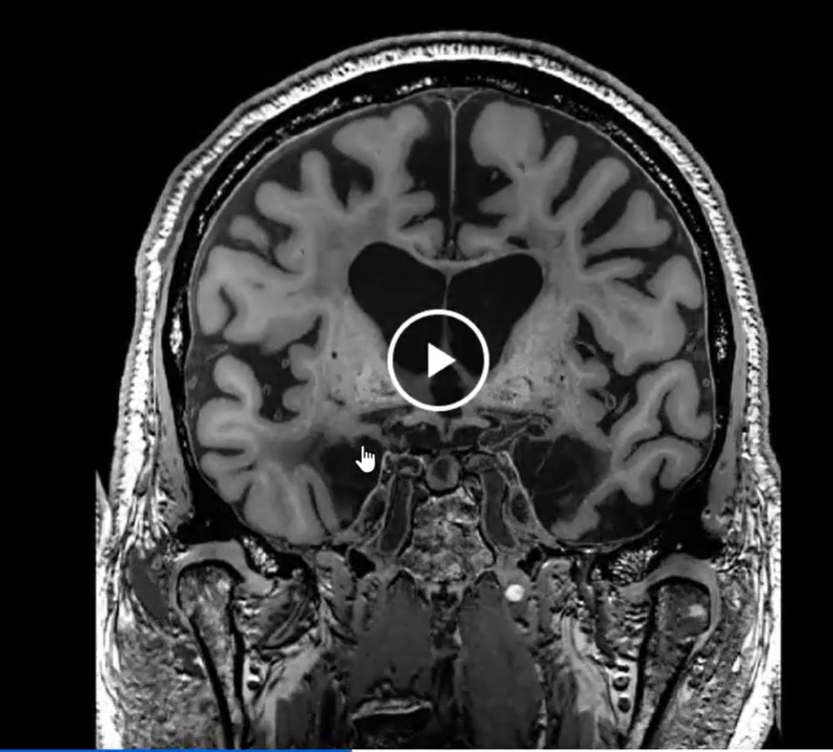

What do H.M.’s brain scans show

A loss of volume in the temporal lobe, where the hippocampus is found